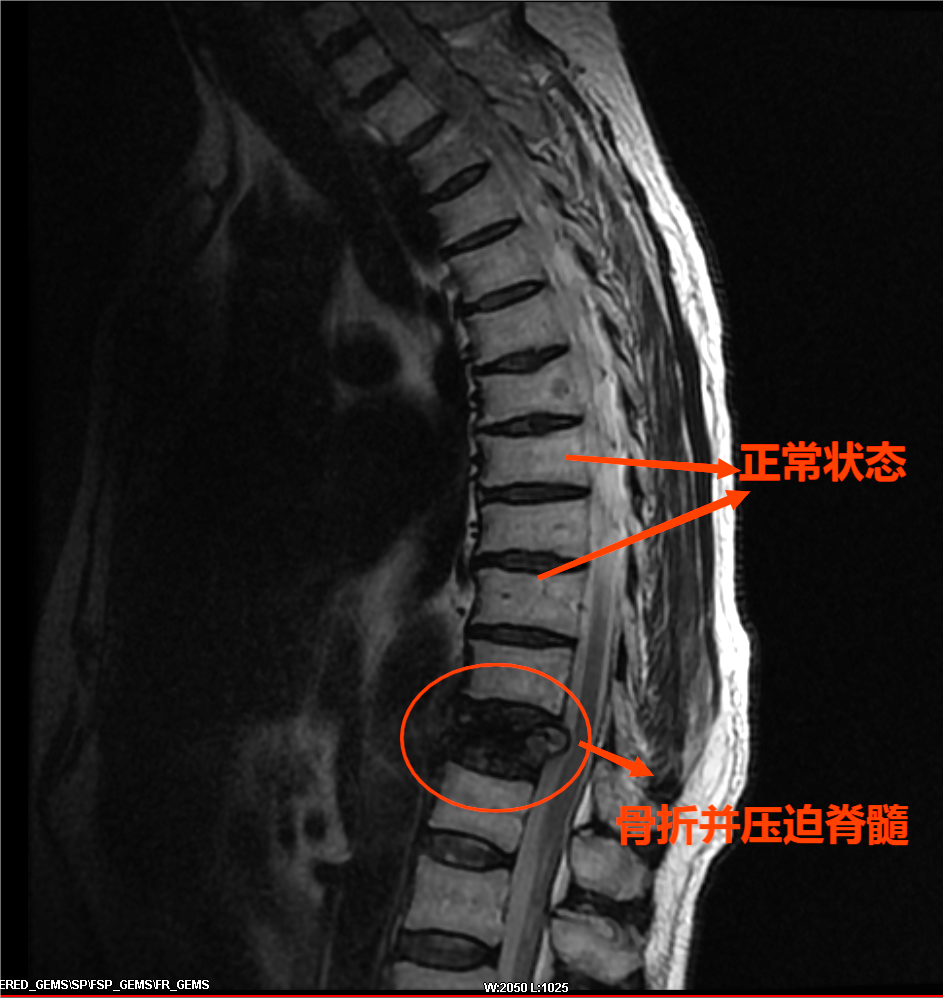

患者在神经脊柱外科诊查后发现:患者骨质疏松非常严重,1年前摔倒至胸椎骨折一直未愈合,此次摔倒进一步使胸椎压缩性骨折,继发椎管狭窄、骨髓水肿等。如任病情发展,患者很快就会瘫痪。

骨质疏松造成压缩性骨折长期不愈合会使椎体高度丢失,发生胸腰段后凸畸形,进一步引发椎管狭窄压迫神经,导致慢性疼痛、残疾、瘫痪等,严重可致患者死亡。